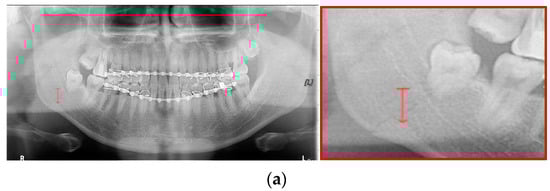

Figure 13.

The comparison of mandibular fracture detection: (a) oral and maxillofacial radiologist, (b) Mask R-CNN (with colored polygons and boxes), (c) YOLOv4 (with a red box), (d) U-Net (with red lines), (e) LAT YOLOv4 (with red boxes), and (f) U-Net with LAT YOLOv4 (with a red box and lines).

In Figure 13, the ramus is misdiagnosed as a fracture. Therefore, Mask R-CNN had the lowest precision score because the misdiagnosis rate was higher than that of the other modules (Figure 16). The YOLO module has a low misdiagnosis rate, while the ‘undiagnosis’ rate is high; therefore, the F1 score is low owing to the ’undiagnosis’ rate. As shown in Figure 11, Figure 12 and Figure 13, YOLOv4 and LAT YOLOv4 have strong advantages over location information; therefore, they tend to detect well in the condyle region, that is, the side fracture, while they tend to detect poorly in the symphysis, body, and angle regions, where location information is ambiguous. Unlike Mask R-CNN and YOLO, U-Net is an image segmentation deep learning network, not an object detection deep learning network and labels mandibular fractures. U-Net marks fractures as lines on the label during training; however, it is difficult to label dislocated fractures, such as condyle fractures (Figure 11). Therefore, in the U-Net module, the side fracture was not diagnosed or misdiagnosed, and the precision-recall score was lower than that of the YOLO modules. It was judged that if the two deep learning networks are used together, the shortcomings of YOLO and U-Net complement each other and help improve mandibular fracture performance. In the proposed module, duplicate boxes that occurred in LAT YOLOv4 were removed before merging with the U-Net. In the proposed U-Net with LAT YOLOv4, the precision score was reduced; however, many ‘undiagnoses’ were eliminated; therefore, the recall score was increased, and it can be observed that the overall F1 score improved the performance by more than 90%.